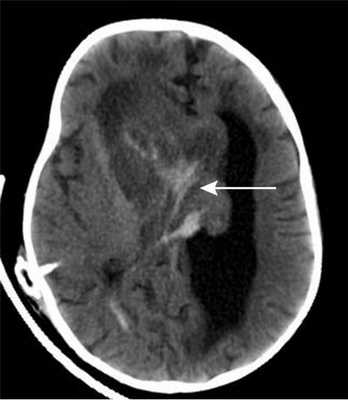

По месту жительства ребенку был установлен вентрикулоперитонеальный шунт, на фоне которого состояние несколько улучшилось — стала активней, аппетит улучшился. При поступлении в Институт нейрохирургии у ребенка развились клонические судороги в левых конечностях с поворотом головы и глаз влево. КТ головного мозга показало наличие свежей крови в строме опухоли, что было расценено, как кровоизлияние в опухоль (рис. 2).

Рисунок 2. Компьютерная томограмма головного мозга грудного ребенка 11 мес с гигантской внутрижелудочковой опухолью. Кровоизлияние в строму опухоли.